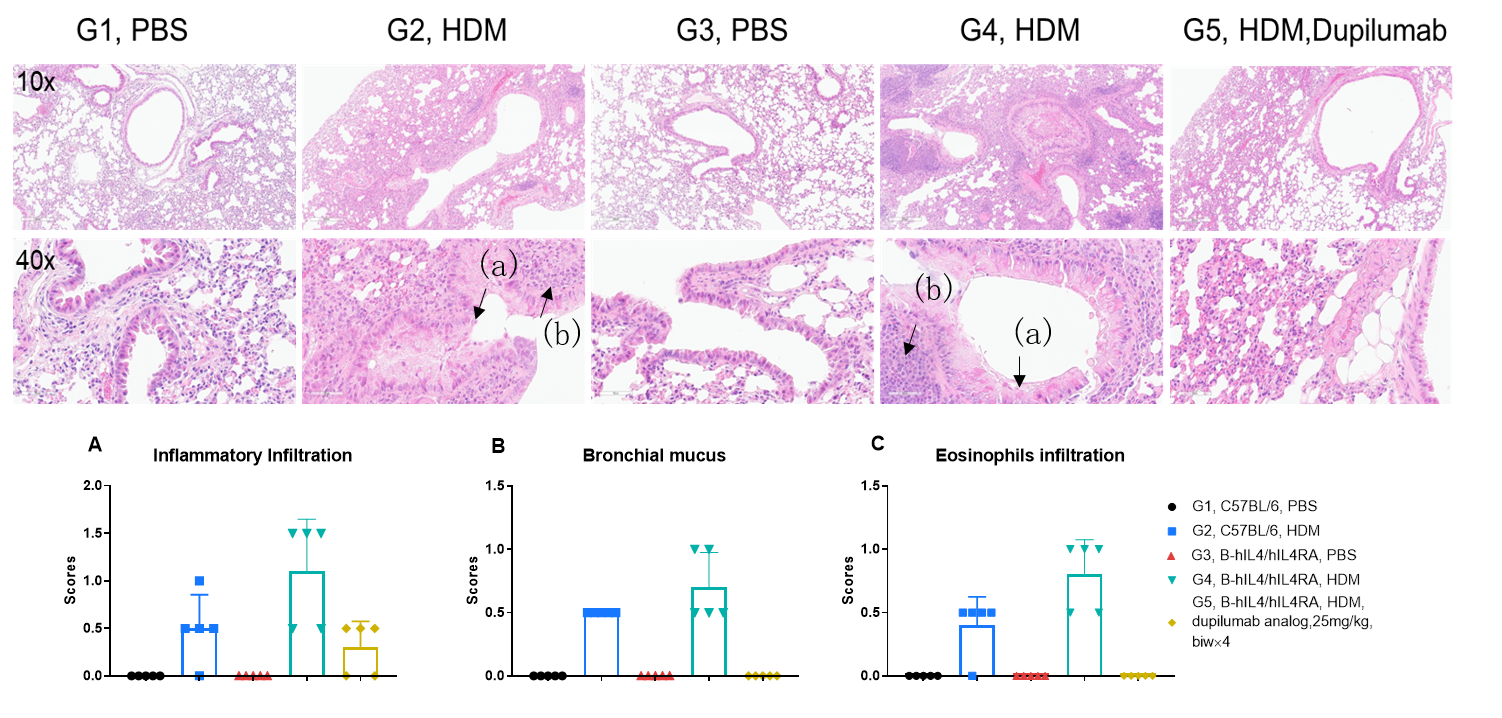

H&E staining in the lungs of asthmatic mice. In contrast to the G1 untreated group, the HDM-treated G2 model group showed asthma-related pathological changes as demonstrated by vascular and peribronchial mixed inflammatory cell infiltration (b) and mucus (a) formation in some bronchi. After administration of dupilumab (in house), the numbers of CD45 + cells and eosinophils were significantly lower compared with the G2 model group.

Efficacy Evaluation of the anti-human IL4RA (dupilumab) (in house) in HDM-induced Asthma Model of B-hIL4/hIL4RA mice. ( A) The number of CD45+ cells in BALF. (B) The number of eosinophils in BALF. (C) The proportion of eosinophils to CD45+ cells. The results showed that after sensitization and challenge with HDM, the leukocyte infiltration of mice in G2 model group was significantly increased compared with G1 control group, and their eosinophil content was significantly increased, suggesting that the model was successfully established. After administration of 25 mg/kg dupilumab (in house), the numbers of CD45+ cells and eosinophils were significantly lower compared with the G2 model group. (D) Serum was taken at the end of the experiment and total IgE levels were measured using ELISA. The results showed that the levels of total IgE in G2 model group were significantly increased compared with G1 control group, suggesting successful modeling. Total IgE levels were significantly lower after administration of dupilumab (in house) drug compared with the G2 modeling group. * P?

H&E staining in the lungs of asthmatic mice. In contrast to the G1 untreated group, the HDM-treated G2 model animals showed asthma-related pathological changes as demonstrated by vascular and peribronchial mixed eosinophil cell infiltration (a) and inflammatory cell infiltration (b) in some bronchi. After administration of dupilumab (in house), the numbers of mCD45+ cells and eosinophils were significantly lower compared with the G2 model group. *** P?